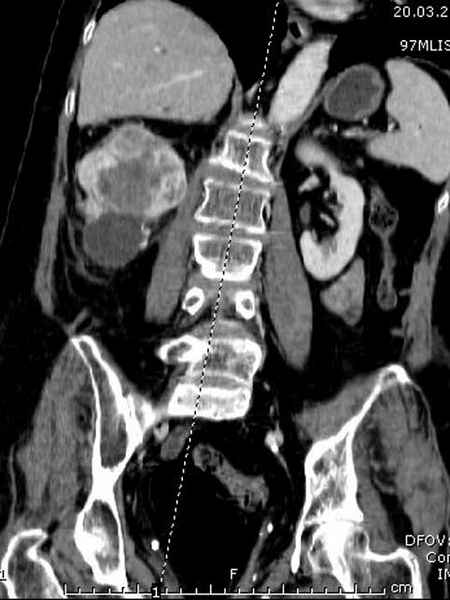

Со слов, больная ничем не болела, только последние 3 месяцев чувствовала боли в бедренной области. КТ брюшной полости подтвердил увеличенную правую почку. (5-6)

Для предупреждения кровотечения во время рассверливания, за день до операции провели эмболизацию сосудов питающий метастаз. http://radiology.rsnajnls.org/cgi/reprint/150/3/673.pdf (7-11, 12-15-16)

С минимальным рассверливанием и ретроградным методом провели остеосинтез бедра 12 мм гвоздем. (17-20)

Кровопотеря во время операции меньше 100 мл.